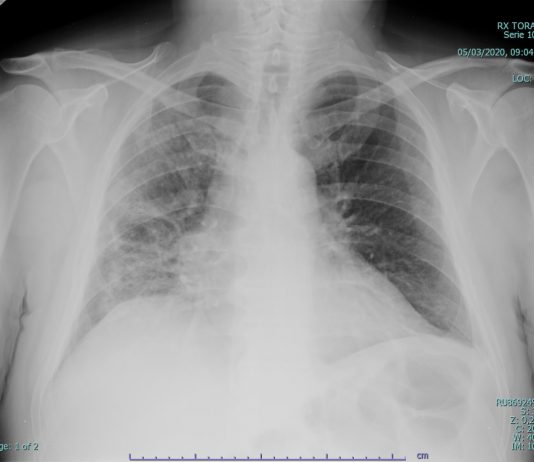

87-years old male

patient with HTA, chronic cardiomyopathy was hospitalized from February 27 to

March 1, 2020 for right-sided heart failure...